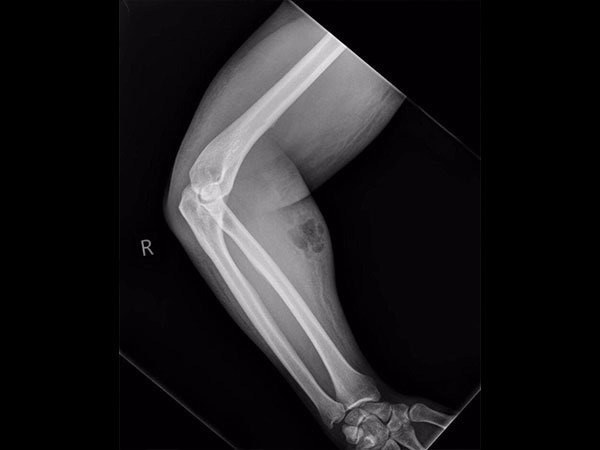

వైద్యులు ఎక్స్ - రే తీసుకుని, అతని శరీరం నుండి వీర్యాన్ని తొలగించేలా చికిత్స చేయడానికి సిద్దపడినా, ఆ వ్యక్తి మాత్రం అందుకు ససేమిరా అంటూ చికిత్సకు నిరాకరిస్తున్నాడు. ప్రస్తుతం అతను వైద్యుల సంరక్షణలోనే ఉన్నాడు. నిజానికి ఇటువంటి వ్యక్తులకు కౌన్సెలింగ్ ఇచ్చాకనే, వైద్యానికి కూడా సిద్దపడవలసి ఉంటుంది.